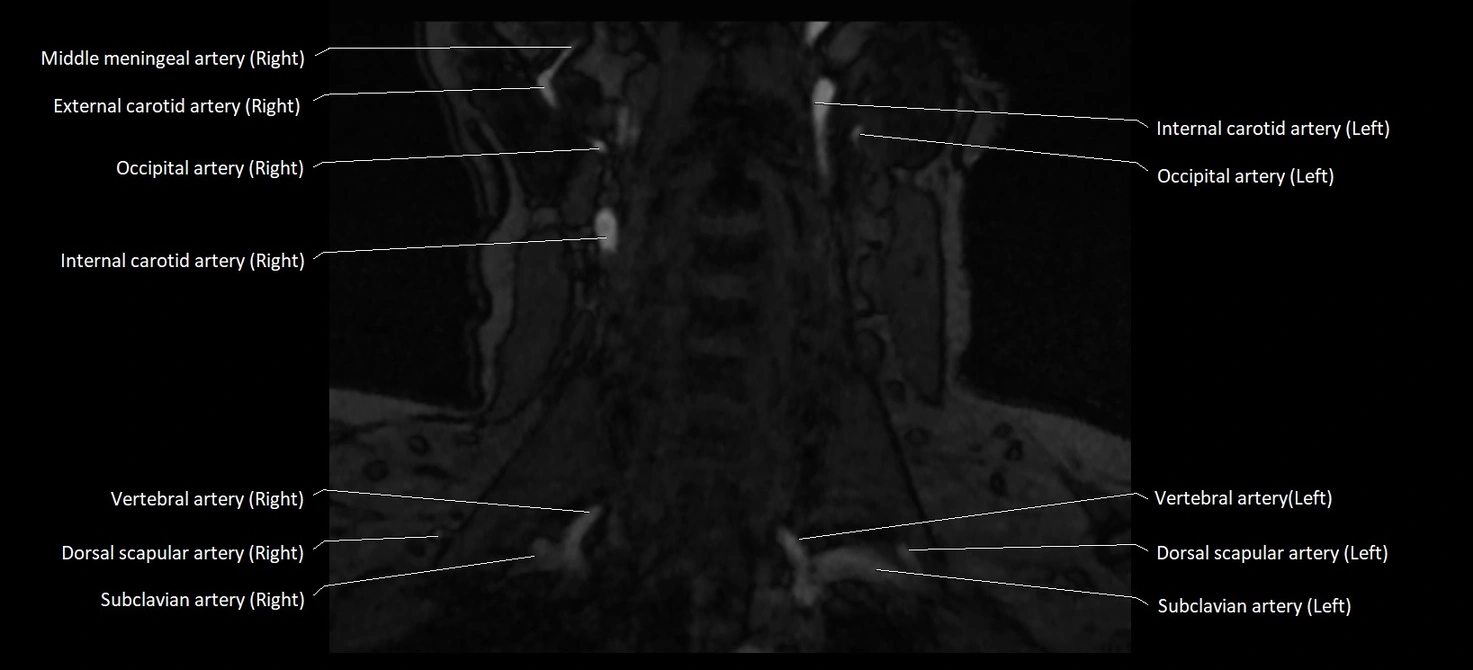

CT image

image